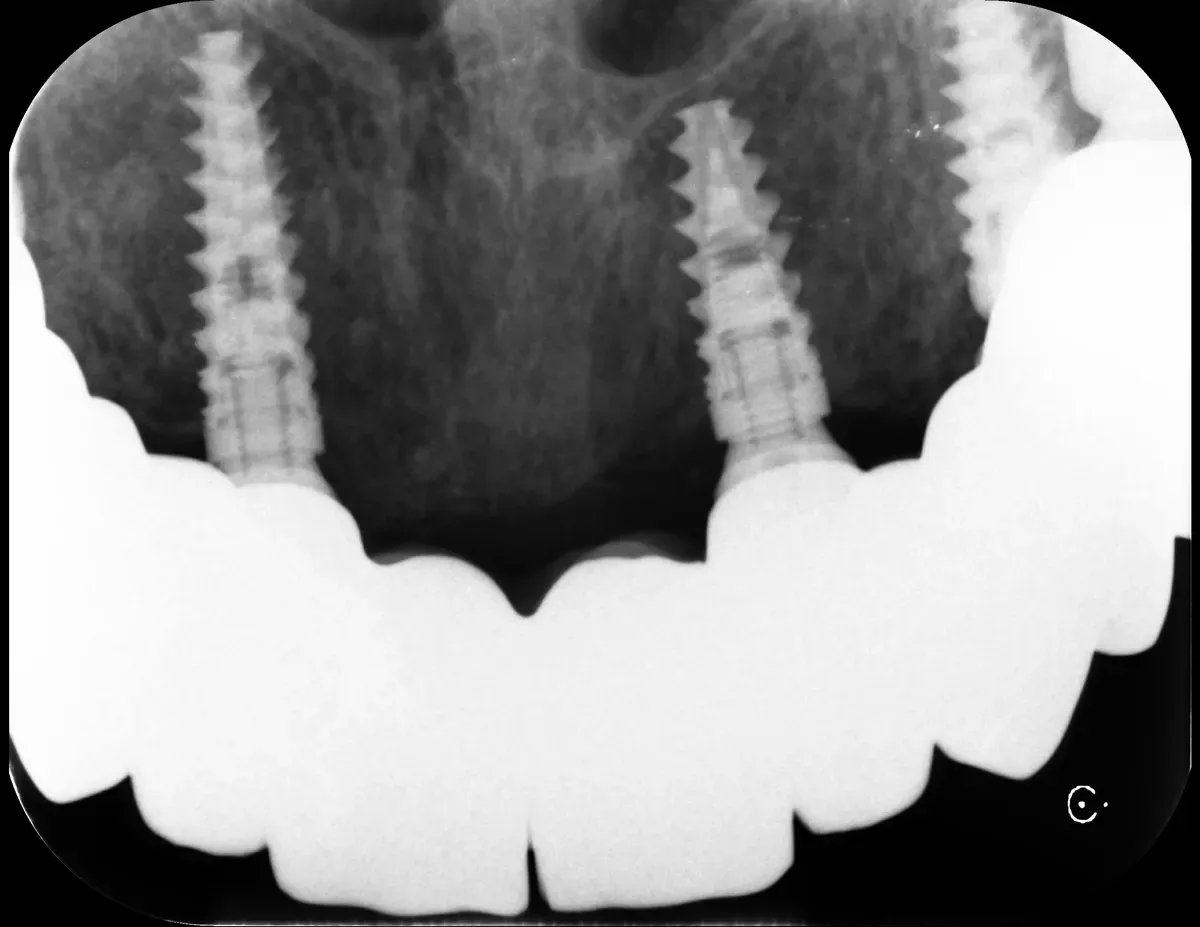

È il fattore numero 1 che determina complessità e costo. Con osso abbondante e di buona qualità si procede con inserimento diretto, guarigione più prevedibile, costi relativamente contenuti. Con osso sottile o riassorbito serve rigenerazione: espansione crestale, innesti, rialzo del seno mascellare.

Le nostre tecniche di espansione crestale (split-crest e rialzo crestale del seno mascellare) permettono spesso di allargare una cresta sottile senza innesti complessi, riducendo costi e tempi.